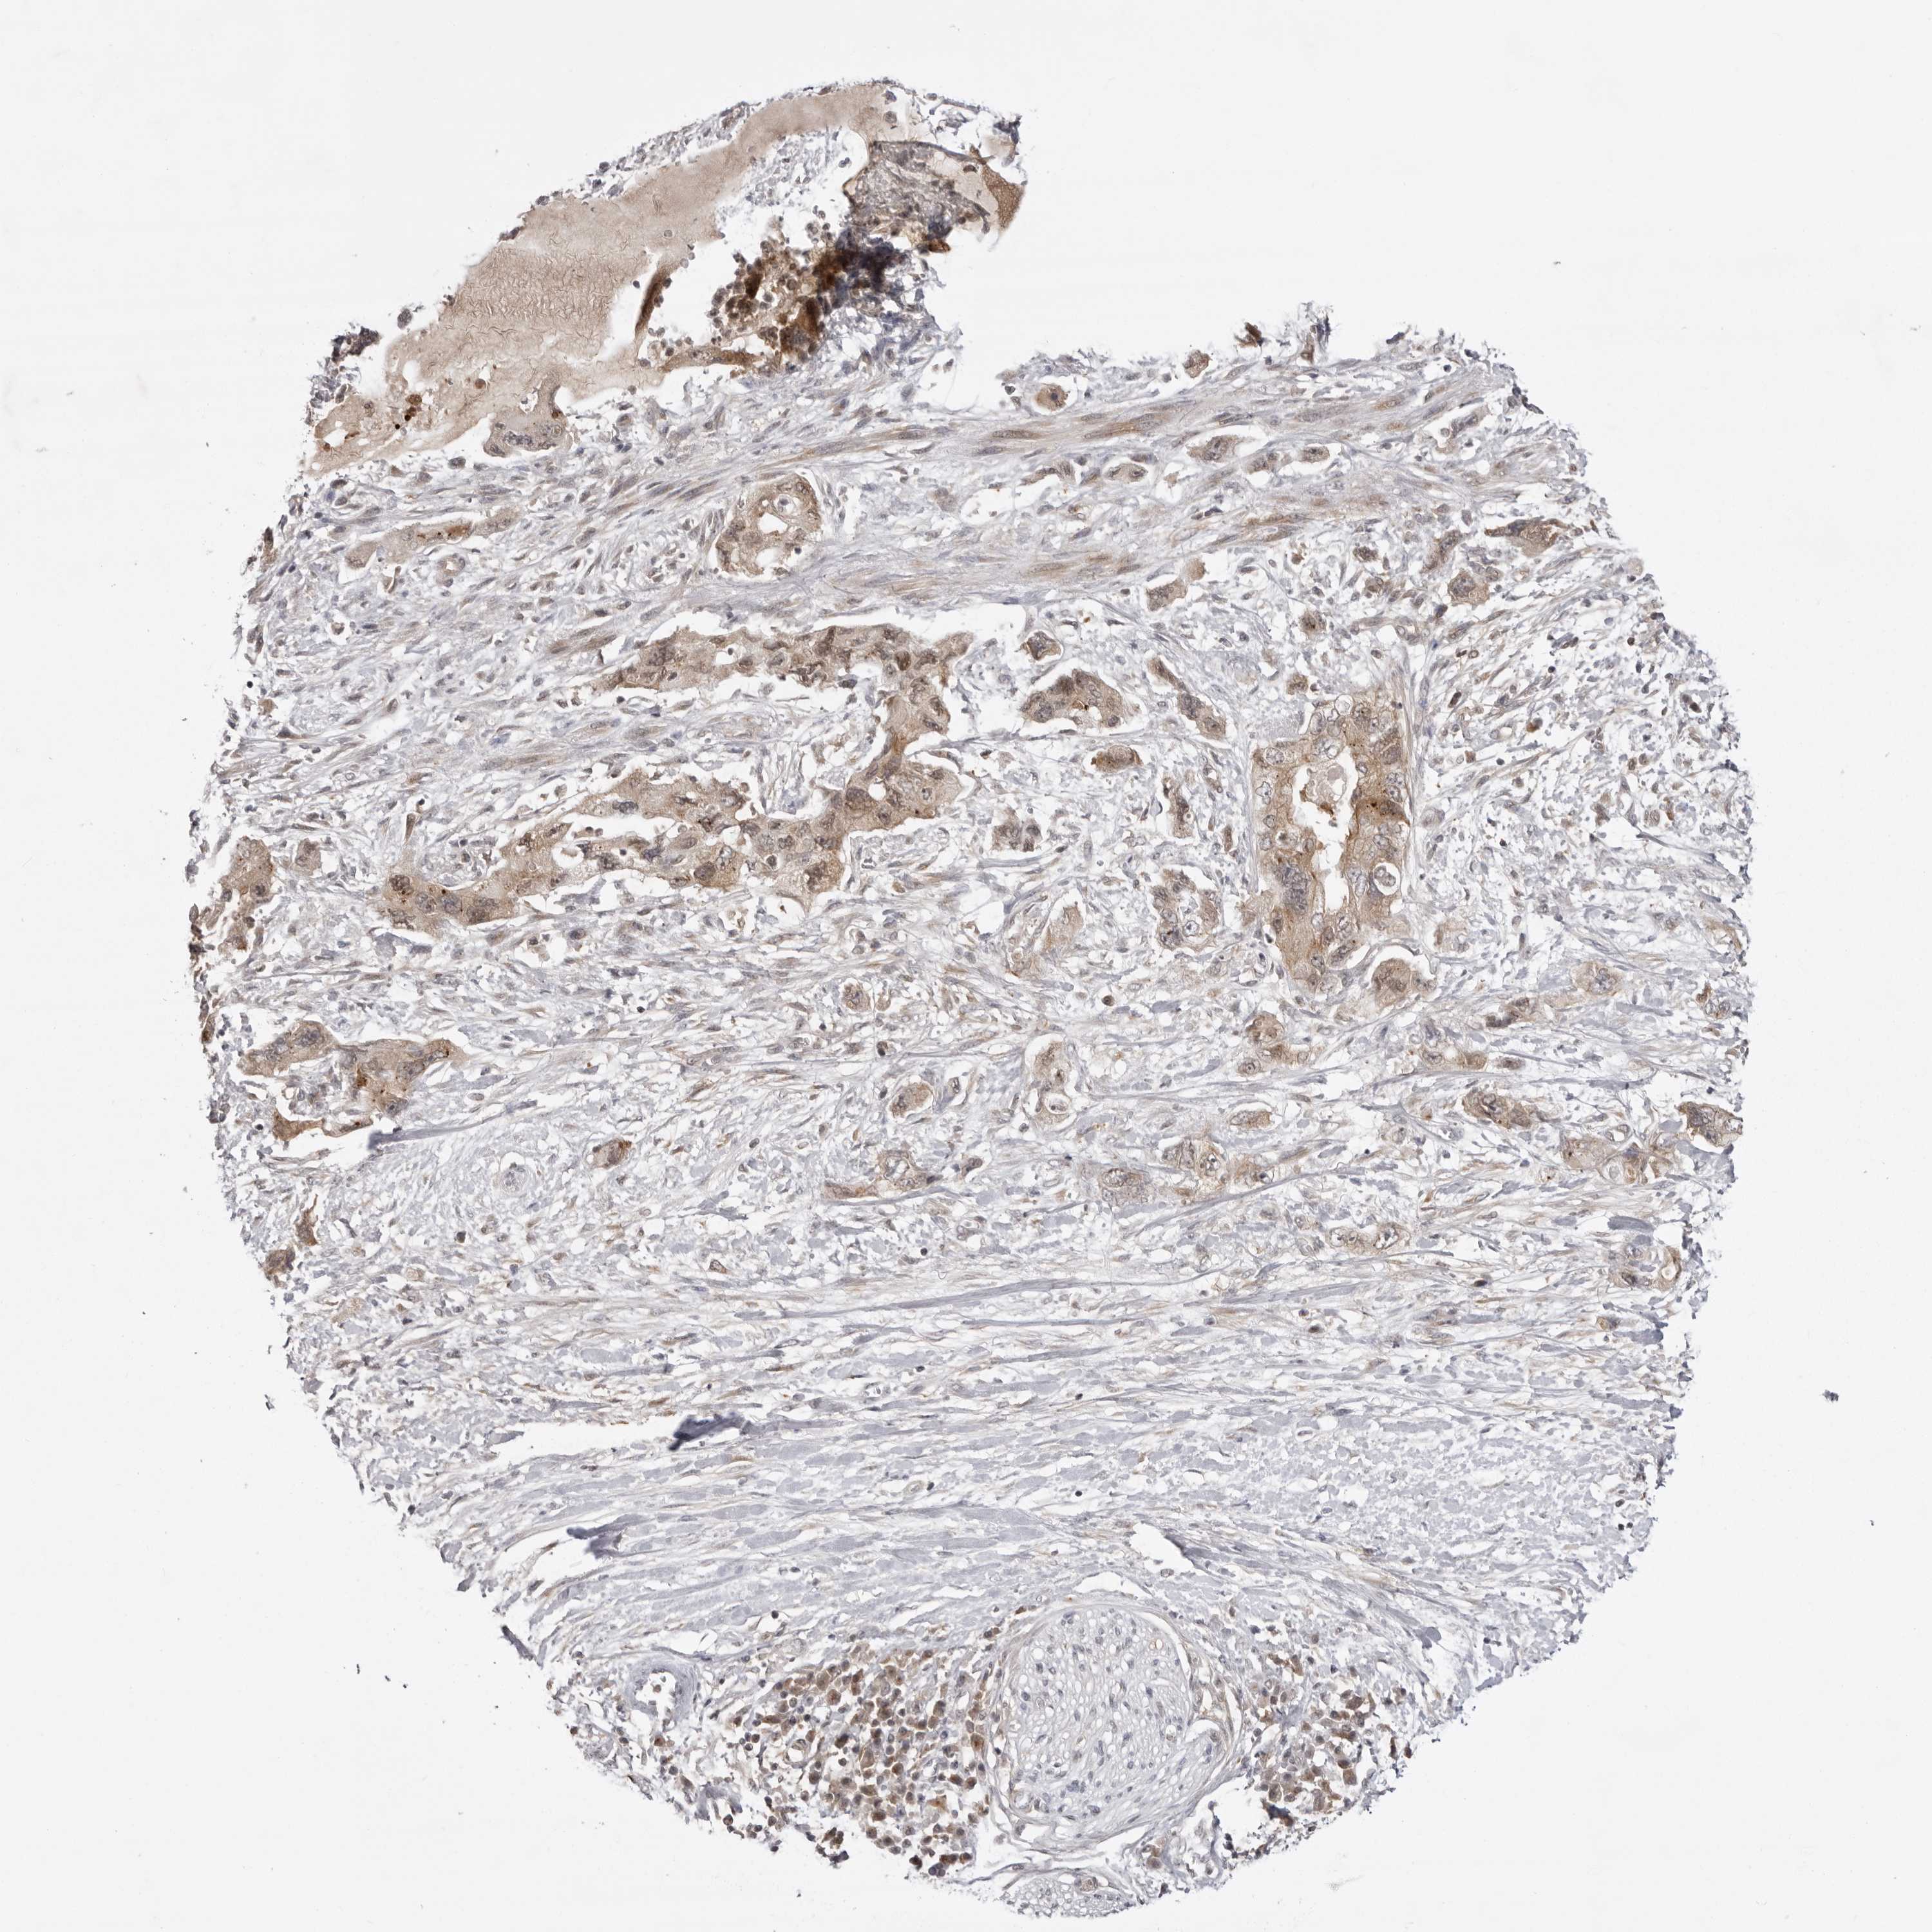

PANCREATIC CANCER - Protein expressioni

A mouse-over function shows sample information and annotation data. Click on an image to view it in a full screen mode. Samples can be filtered based on level of antibody staining by selecting one or several of the following categories: high, medium, low and not detected. The assay and annotation is described here.

Note that samples used for immunohistochemistry by the Human Protein Atlas do not correspond to samples in the TCGA dataset.

Antibody stainingi

Antibody staining in the annotated cell types in the current human tissue is reported as not detected, low, medium, or high, based on conventional immunohistochemistry profiling in selected tissues. This score is based on the combination of the staining intensity and fraction of stained cells.

Each image is clickable and will lead to virtual microscopy that enables deeper exploration of all samples and also displays staining intensity scores, fraction scores and subcellular localization as well as patient and tissue information for each sample.

Antibody HPA023389

Antibody HPA027762

Staining

High

Medium

Low

Not detected

Intensity

Strong

Moderate

Weak

Negative

Quantity

>75%

75%-25%

<25%

None

Location

Nuclear

Cytoplasmic/membranous

Cytoplasmic/membranous,nuclear

Adenocarcinoma, NOS